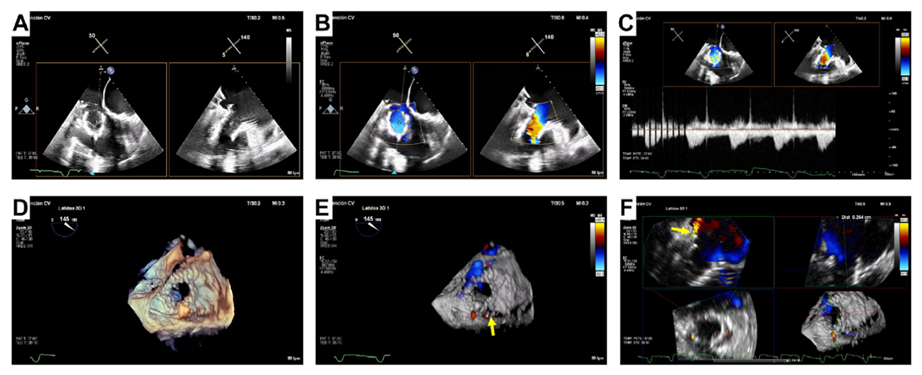

基線經(jīng)胸和經(jīng)食道超聲